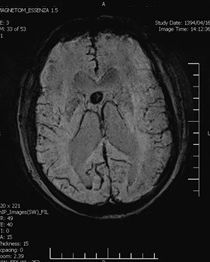

An Occipital Headache as the First Presentation of Multiple Third, Fourth, and Lateral Ventricular Cavernous Malformations: A Case Report and Review of Literature

Background: Cavernous hemangiomas are common benign vascular malformations. Their existence in the intraventricular region is very rare. Case Reports: A 43-year old woman with an occipital headache was admitted to the emergency ward. Brain computed tomography scan showed mild hydrocephalus and multiple intraventricular isodense lesions. Imaging findings, especially of Gradient Resonance Echo imaging, were in favor of multiple intraventricular cavernous malformations. Conclusion: This is a rare presentation of multiple cavernous malformation as occipital headache without needing surgical intervention in this phase. Coexistence of periventricular plaques like Radiologically isolated syndrome of Multiple sclerosis is another unique aspect in this report. [GMJ.2017;6(1):61-65]